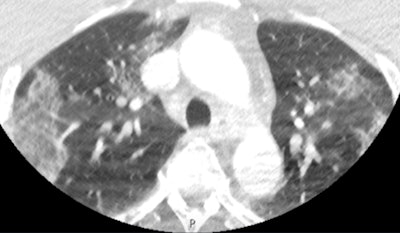

Researchers from a top London facility have highlighted a simple and accurate COVID-19 diagnostic and prognostic imaging biomarker obtained from CT angiography (CTA) lung apices: the presence or absence of ground-glass opacification (GGO). They think their findings have major implications for management of patients with suspected stroke through early identification of COVID-19 and the limitation of disease transmission.

"At the very start of the pandemic, we noticed the ground-glass opacification (GGO) and thought this had the potential to be a useful biomarker," study lead and corresponding author Dr. Tom Booth, PhD, told AuntMinnieEurope.com. "However, what was very surprising was how this simple biomarker outperformed all the many other clinical markers we also analyzed."

"We also were surprised that the simplest measure -- i.e. the presence or absence of GGO -- was accurate and reliable compared to more nuanced and refined descriptions regarding, for example, exact location or whether focal or not," added Booth, who is a consultant neuroradiologist at King's College Hospital (KCH) and senior lecturer in neuroimaging in the School of Biomedical Engineering & Imaging Sciences at King's College London. "This is important as it is easy for radiologists who are not thoracic radiologists -- and likely clinicians and radiographers -- to interpret the sign."

Apical GGO was present in 22.2% (50/225) of patients. GGO had high interrater reliability (Fleiss k = 0.81; 95% confidence interval [CI], 0.68-0.95), and compared with RT-PCR tests, it had good diagnostic performance (sensitivity, 75% [95% CI, 56-87]; specificity, 81% [95% CI, 71-88]; odds ratio = 11.65 [95% CI, 4.14-32.78]; p = 0.001) on multivariate analysis.

In contrast, all other contemporaneous demographic, clinical, and imaging features available at CTA were not diagnostic for COVID-19, the authors wrote. The presence of apical GGO was an independent predictor of increased 30-day mortality (18% versus 5.7%, p = 0.017; hazard ratio = 3.51; 95% CI, 1.42-8.66; p = 0.006).